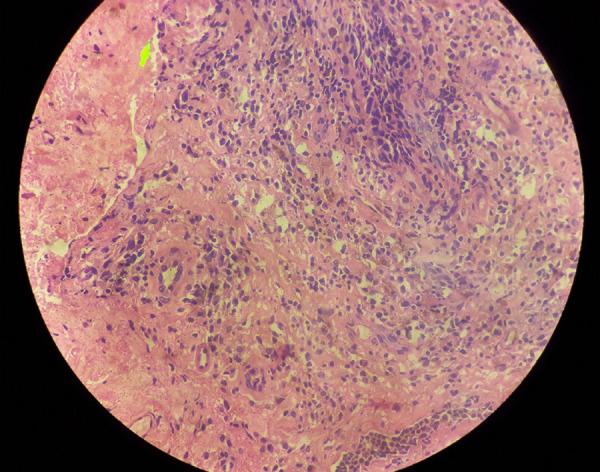

Plasma cell vulvitis is a rare inflammatory disorder of the vulva with an unknown aetiology, characterised by mucosal inflammation. It commonly manifests as pain, itching, dyspareunia, and dysuria and clinically presents as erythematous plaque and macules on the vulva. This condition is refractory to available treatment modalities in the literature. We present a case of a 70-year-old female with histopathologically proven plasma cell vulvitis treated by platelet-rich plasma therapy after multiple failed treatment attempts with topical steroids and immunomodulators. The patient improved both symptomatically and clinically on follow-up with platelet-rich plasma therapy. Platelet-rich plasma which is a new novel treatment can be a therapeutic option for recalcitrant cases of plasma cell vulvitis.

浆细胞性外阴炎是一种罕见的外阴炎症性疾病,病因不明,以黏膜炎症为特征。它通常表现为疼痛、瘙痒、性交困难和尿痛,临床上表现为外阴红斑和斑块。这种情况对文献中现有的治疗方法有抵抗力。我们报告了一例 70 岁女性的病例,该患者经组织病理学证实为浆细胞性外阴炎,在外用类固醇和免疫调节剂多次治疗失败后,接受了富血小板血浆治疗。该患者在接受富血小板血浆治疗后症状和临床均有改善。富血小板血浆是一种新的治疗方法,可为难治性浆细胞性外阴炎病例提供治疗选择。